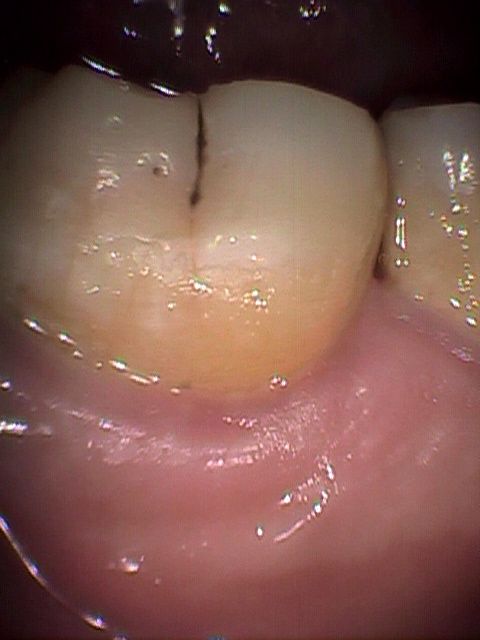

「う歯」や歯周病は【複雑な病気】であり、単純な治療仮説や技能だけでは治療困難です。

私たちが最も認めたくない心身を支配する存在は「加齢」です。中高年になれば認めたくなくとも、これが最上位に位置します。表面的な元気さにかかわらず「加齢」により心身の劣化は進行いたします。歯に於いては咬耗症や「象牙質・歯髄複合体」の免疫力低下、歯周組織では「歯肉毛細血管梗塞や管壁の老化」などの様々な負の変化をもたらします。

5.1.病的組織と炎症性産物の除去

感染症治療は【除菌】と【壊死組織や炎症性産物の除去】を並行に処理します。 理由は感染病巣において高圧、高速の切削や回転機器を使用すれば、例え、慎重にこれらの器械を操作しても微細な病原菌の拡散を防止することは困難です。

そのため、二次感染防止のために「う歯】の切削時、あるいは歯周ポケットに対する処置の際は【壊死組織や炎症性産物に付着している病原菌】の除菌(殺滅)をしながら治療致します。